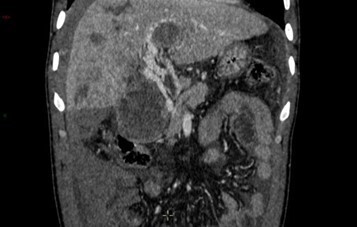

Le patient est finalement stabilisé hémodynamiquement, permettant son transfert en radiologie, et le scanner suivant est réalisé.

Question 11 - Sur ce scanner vous observez (une ou plusieurs réponses exactes) :

Le scanner retrouve de multiples masses intra-hépatiques infiltrantes. L’une d’entre elles, dans le segment V, est partiellement exophytique (bombant en sous-capsulaire) avec en son sein une flaque de produit de contraste. Par ailleurs, on retrouve une thrombose portale extensive de l’ensemble du système porte.

Au contact et le long de la gouttière pariéto-colique droite : un épanchement liquidien abondant, hétérogène, avec une composante spontanément hyperdense évocatrice de sang frais.

Le tout est donc évocateur, compte tenu par ailleurs des antériorités du patient, d’une progression de la maladie avec un CHC infiltrant bi-lobaire, rompu dans la cavité péritonéale avec saignement actif.